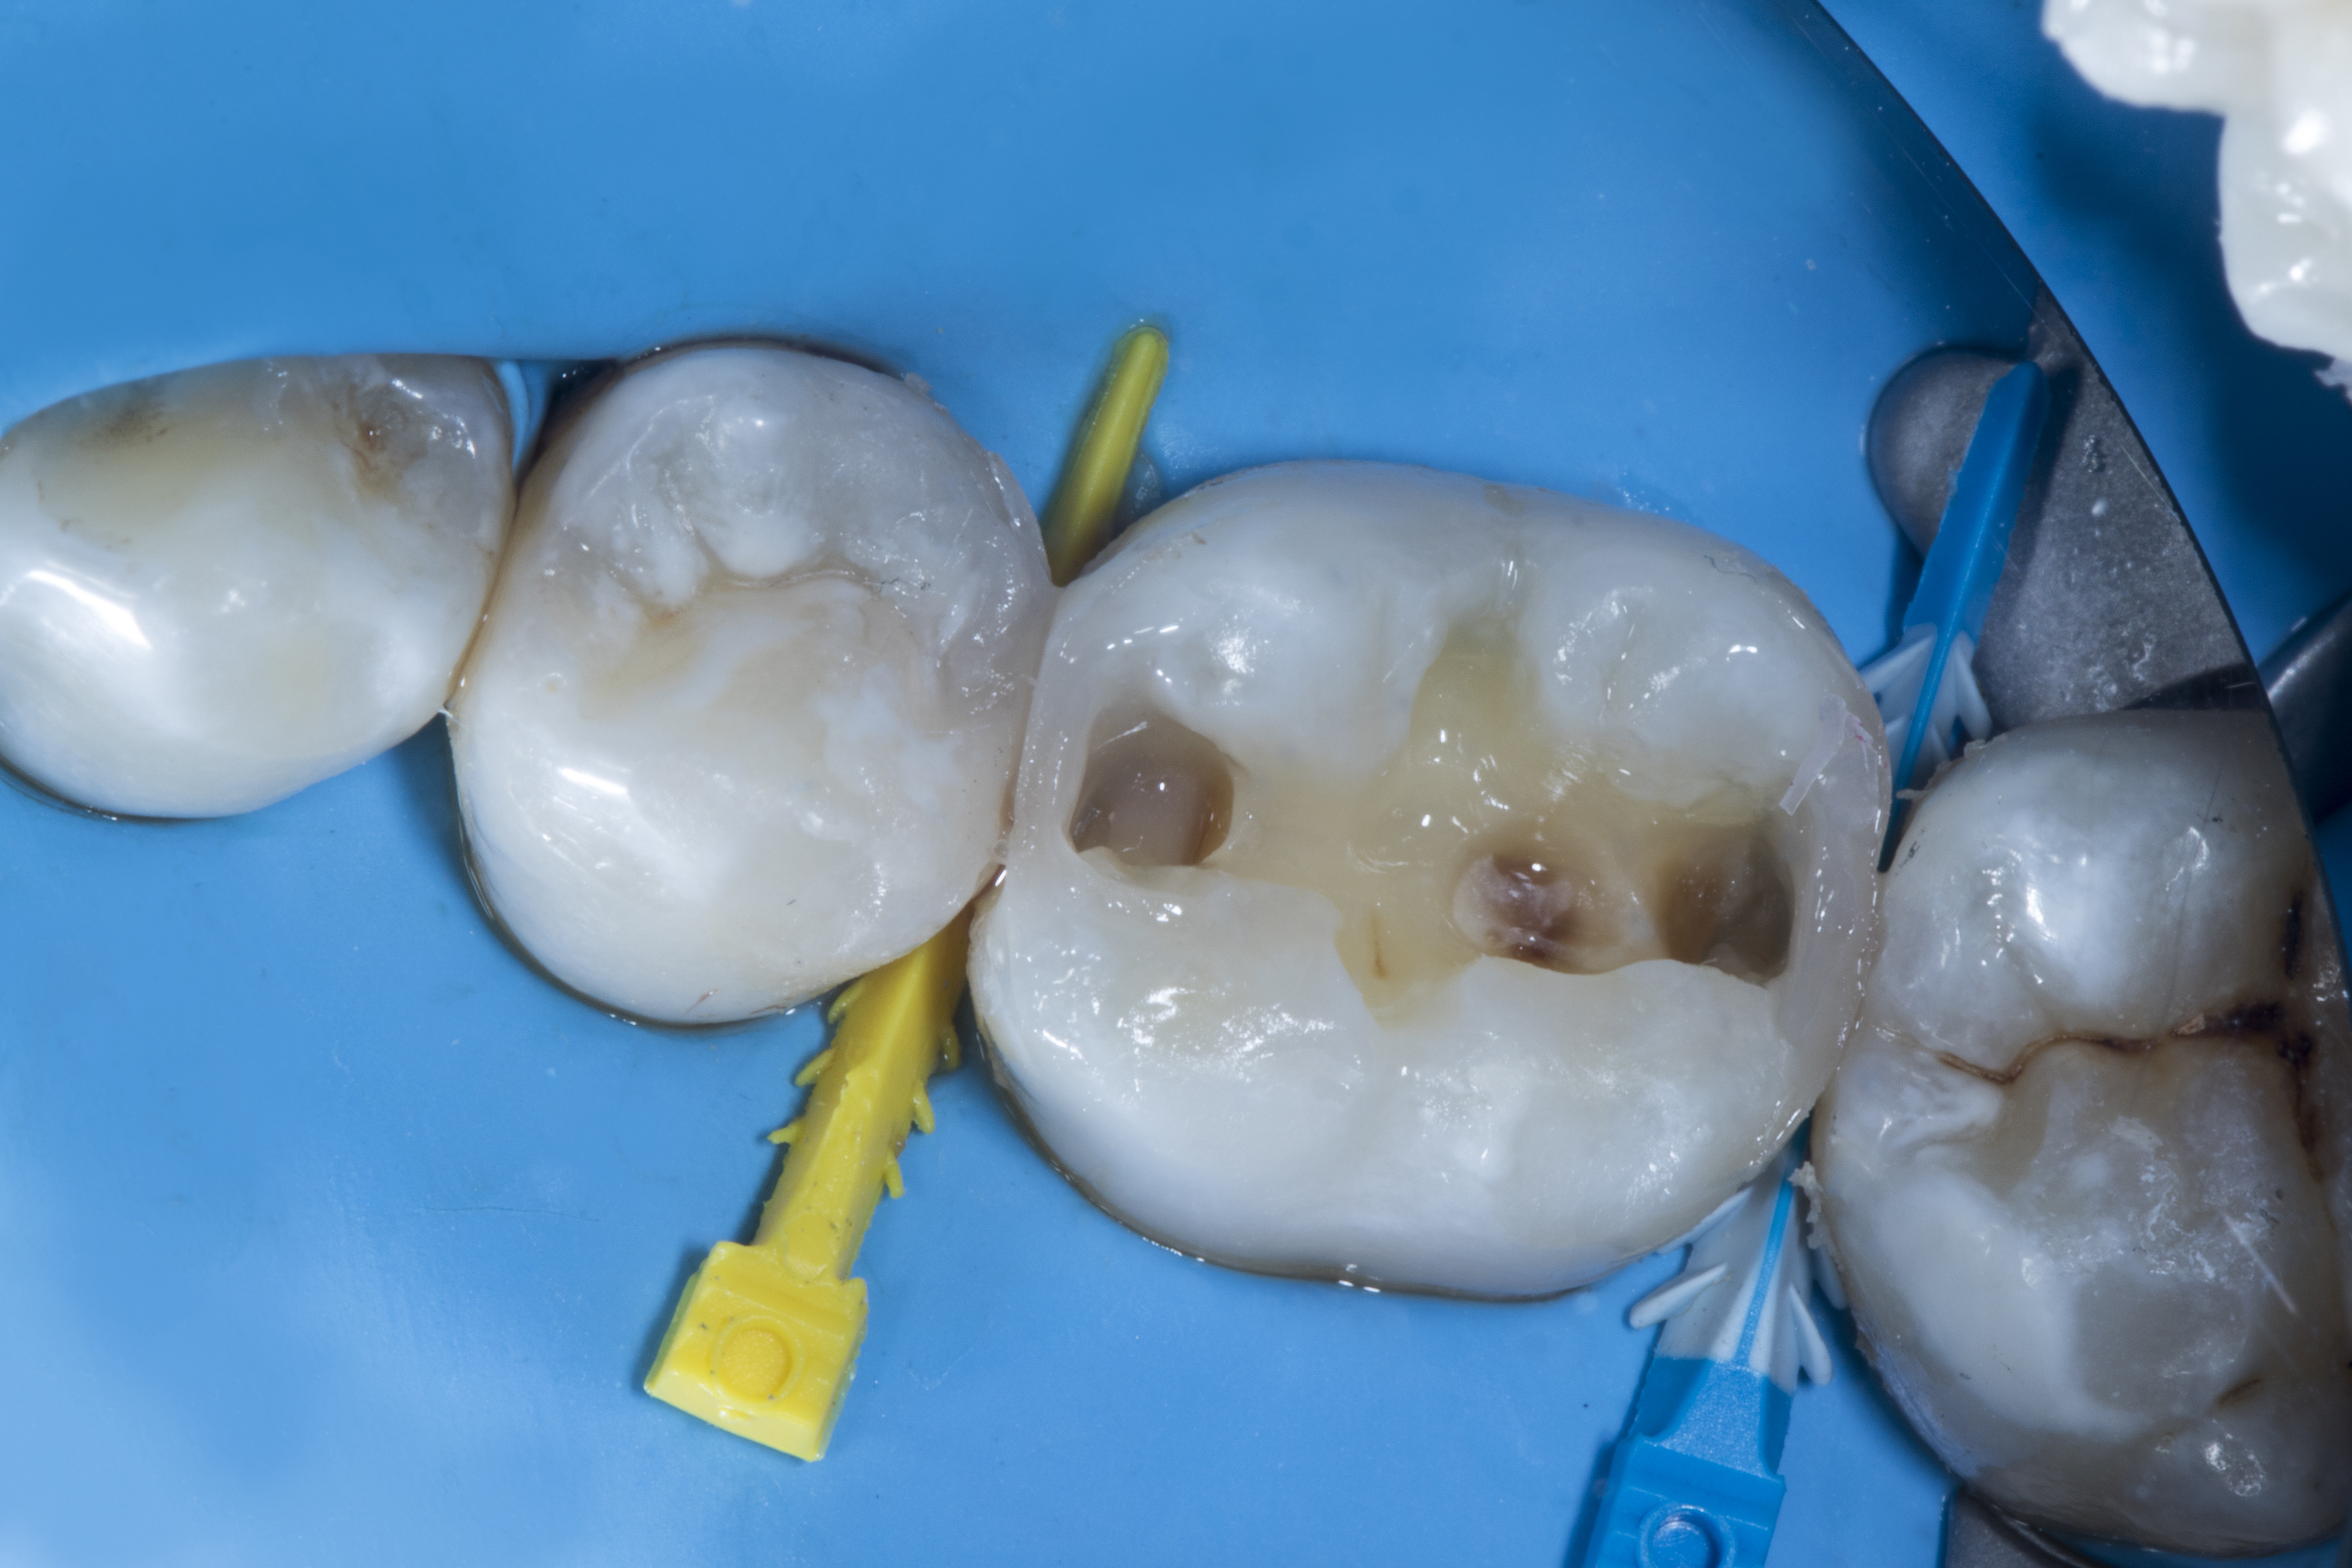

Step 2 – Restoration of tooth #35. After the initial cavity preparation, a deeper carious lesion was identified. Caries dye was applied to effectively remove caries with the help of a slow speed round carbide bur.

Figure 2

Figure 2. After the initial cavity preparation a deeper carious lesion was identified.